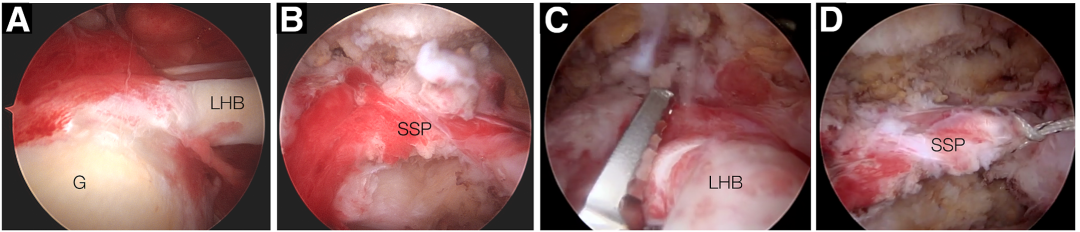

详尽的病史、功能评估、临床检查和放射学评估至关重要(图 1)。磁共振成像用于评估肌肉萎缩、肌腱回缩和脂肪浸润。

图1. 一例65岁男性患者右肩的术前磁共振成像(MRI)。(A)冠状位显示大面积后上肩袖撕裂。冈上肌腱呈Patte III级回缩(白色箭头)。(B)轴位可见肱二头肌长头腱病变(黑色箭头)。但肌腱仍保持完整。(C)矢状旁位显示肌肉萎缩。按Goutallier等[12]分级为2级脂肪浸润。星号指示冈上肌。